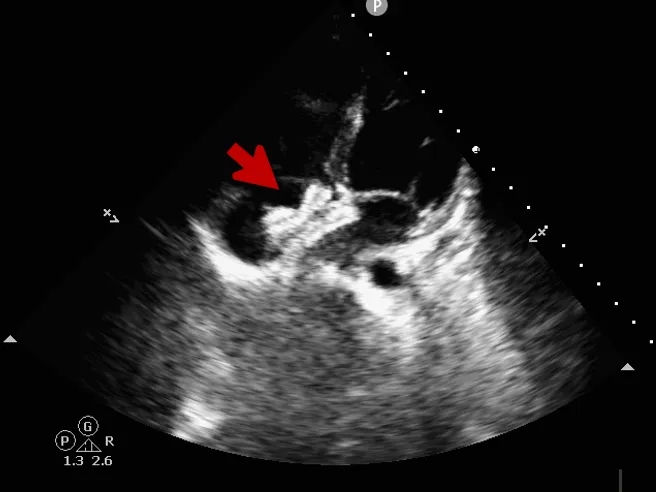

锁定后评估

心尖四腔心切面可见封堵器形态良好

主动脉短轴切面可见封堵器呈“Y”字型抱住主动脉

彩色多普勒血流成像显示无残余分流存在